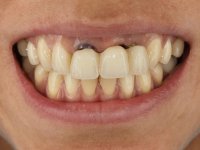

Female patient, 30 years old, non-smoker. The patient appeared in consultation after orthodontic treatment and placement of an implant at tooth site 2.1. Teeth 3.7, 3.6 and 4.7 had root canal therapy and teeth 1.5, 2.5, 2.6 and 4.5 had undergone extensive restorations. Patient had a thin periodontium and showed a satisfactory oral hygiene. After surgical exposure of the implant, it proved to be positioned improperly. Prosthetic rehabilitation of the implant proved impossible by adopting acceptable aesthetic criteria. The patient carried an acrylic temporary crown on a stump screwed as a fallback solution for six years, as she had not accepted the offer to remove the implant. After this time, patient returned to consultation with an abscess in tooth 1.1. After analyzing the situation, it was verified that teeth 1.1 and 2.2 had indicated extraction and the implant should be removed or submerged.

In the initial phase, it was proposed to the patient to perform the surgical implant exposure and after clinical evaluation, make prosthetic decisions. Once the healing screw was placed and the soft tissues were healed, an inadequate position of the implant was found. In view of the dramatic situation, the patient was proposed to remove the implant and put a new one after tissue regeneration. This proposal was rejected by the patient, who suggested temporary rehabilitation of the current implant. A new proposal was then made, to rehabilitate the implant, consisting of a screwed abutment, and on this, the placement of an acrylic crown with coronal and gingival components. After 6 years with the provisional treatment, the patient appeared in consultation with an abscess in tooth 1.1. After clinical and imaging analysis, it was decided to remove teeth 1.1 and 2.2, submerge the implant, place two implants at the site of 1.1 and 2.2 and perform adequate tissue regeneration. Temporization would be done with a provisional 3-element bridge, adhered with a net to the neighboring teeth. After osseointegration, definitive rehabilitation would be done with a 3-element bridge, including zirconia infrastructure and ceramic cover.

The surgical implant exposure and the healing screw placement proved to be a negative surprise regarding its position. Since the proposed removal of the implant was refused, we advanced to its provisional rehabilitation. An open tray impression technique was done, and a screwed abutment with a coronal and gingival component and an acrylic crown were made in the laboratory, using these two components. The provisional crown was placed in the mouth until a final decision was made. Six years passed before the patient returned to the clinic with an abscess on tooth 1.1. The choice to remove teeth 1.1 and 2.2 was made, to create a provisional 3-element bridge with a net to be adhered to the adjacent teeth. Surgery was planned and performed, placing the two implants at the site of 1.1 and 2.2, and the implant at the 2.1 site was cut with the objective of submerging it, while adequate tissue regeneration was performed (Surgical Work performed By Dr. Manuel Neves). During osseointegration, the patient used the fixed provisional bridge. A first impression was made for confection of a zirconia screwed provisional bridge, which worked the soft tissues for twelve weeks. The definitive impression was made with the individualisation of custom impression copings. Final rehabilitation was done with ceramized abutments, and also a bridge with zirconia infrastructure and ceramic cover. Due to the inclination of the implant placed at the site of tooth 1.1, the bridge required cemented fixation.